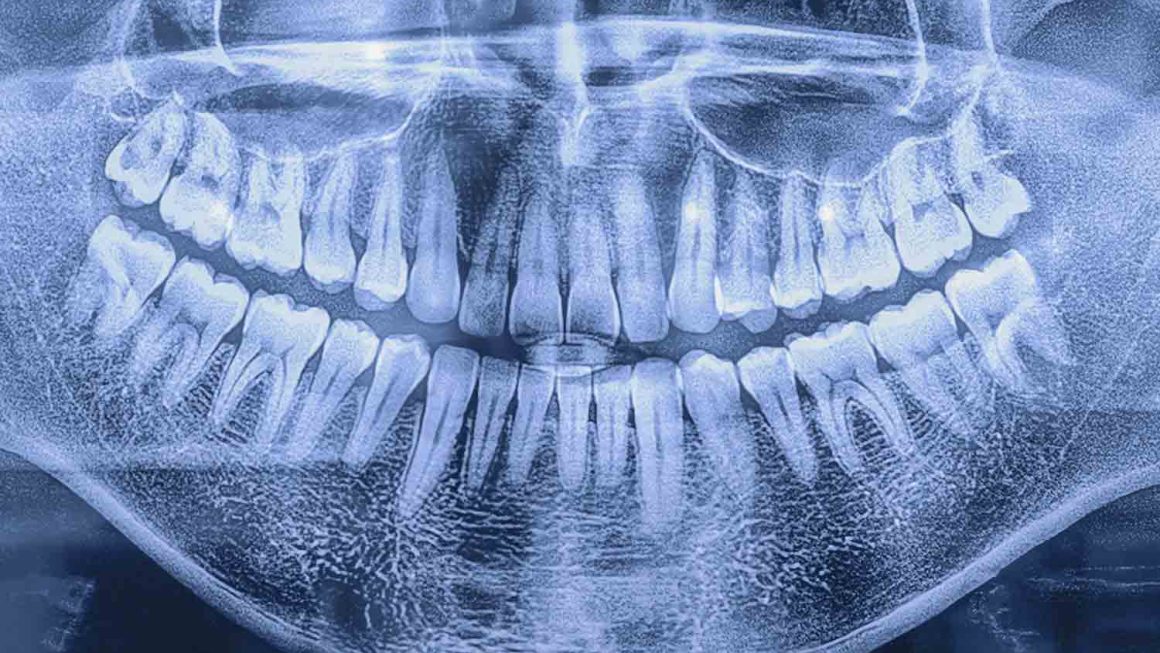

As we mentioned earlier, the total costs of dental implants can vary greatly depending on each patient’s case. Some will need single implants while others may require full arches. Additionally, the physical characteristics of each patient’s mouth will factor into the work that will be required and ultimately the type and price of the implants. Finally, dental X-rays are often the only way to identify tiny cavities in primary (baby) teeth.